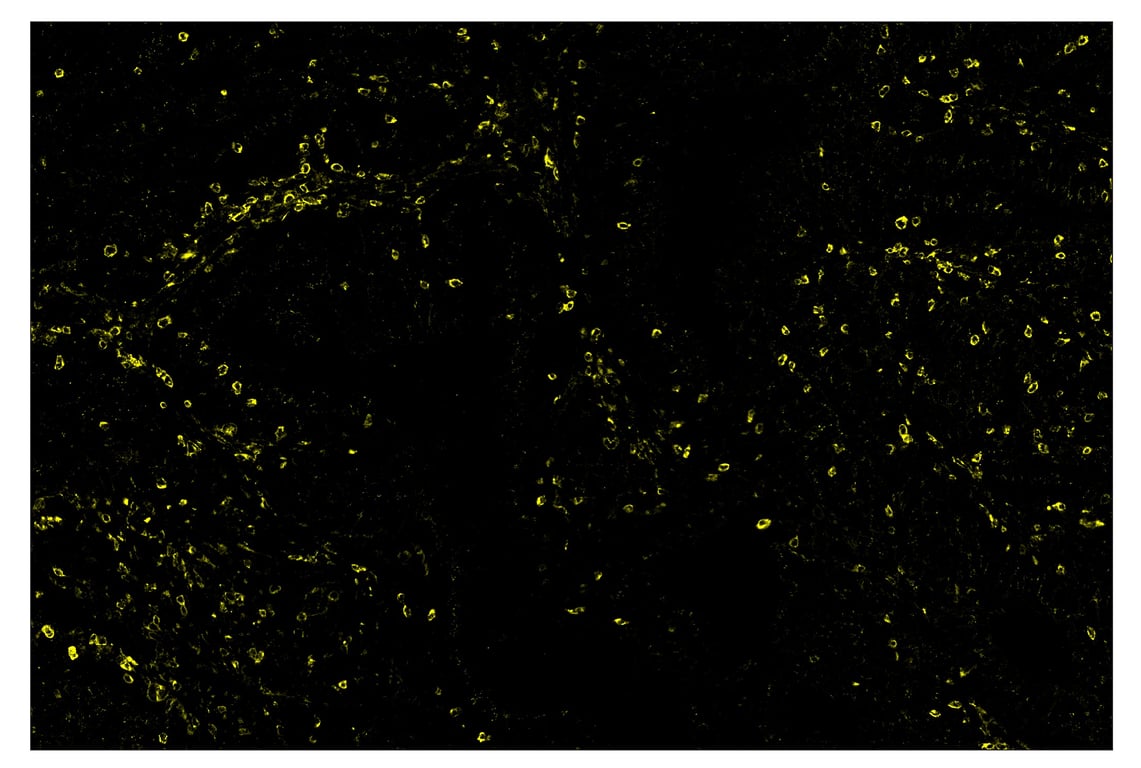

SignalStar™ immunohistochemical analysis of paraffin-embedded human colorectal adenocarcinoma using TIM-3 (D5D5R™) & CO-0010-594 SignalStar™ Oligo-Antibody Pair #55508 (yellow). All fluorophores have been assigned a pseudocolor, as indicated. Staining was performed on the BOND RX by Leica Biosystems.

Immunohistochemistry Image 3: TIM-3 (D5D5R<sup>™</sup>) & CO-00010-488 SignalStar<sup>™</sup> Oligo-Antibody Pair